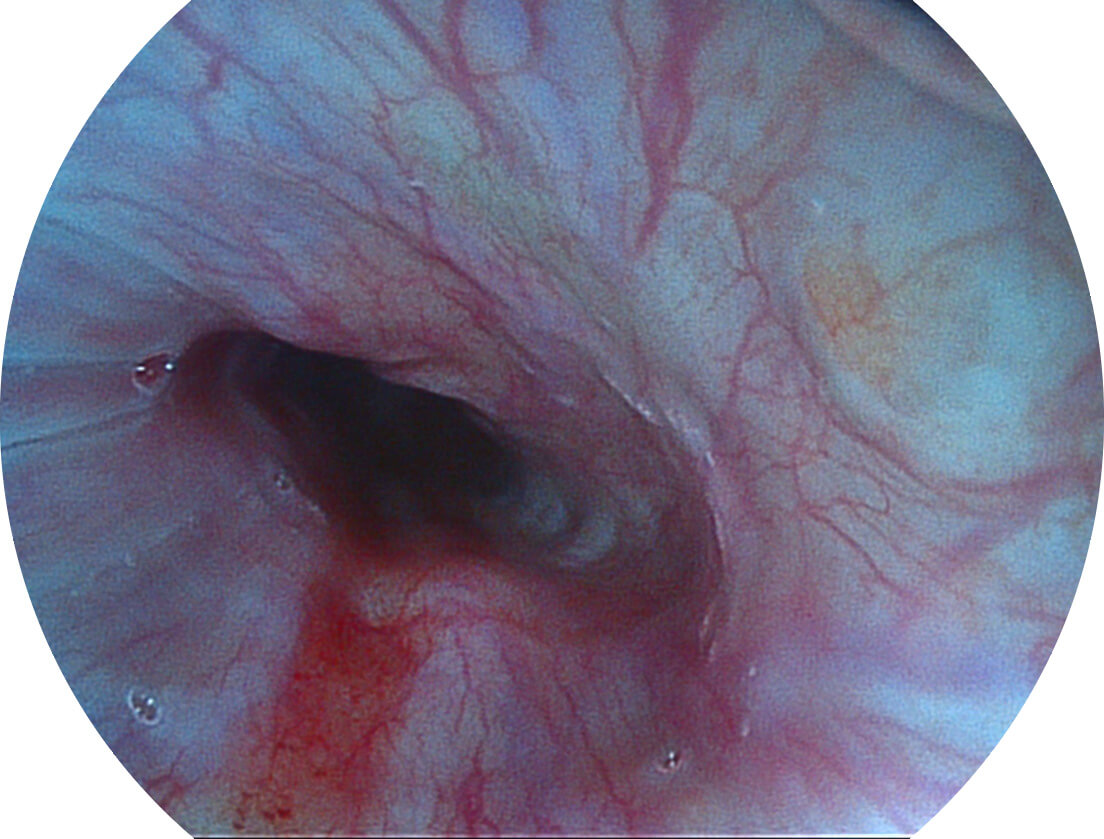

白光图像

SFI图像

图像具有高亮度、高黏膜血管颜色对比度的特点,且不改变粘液、食物残渣、粪便的基本颜色,可在中远景下进行观察,助力消化道早期疾病的诊断。